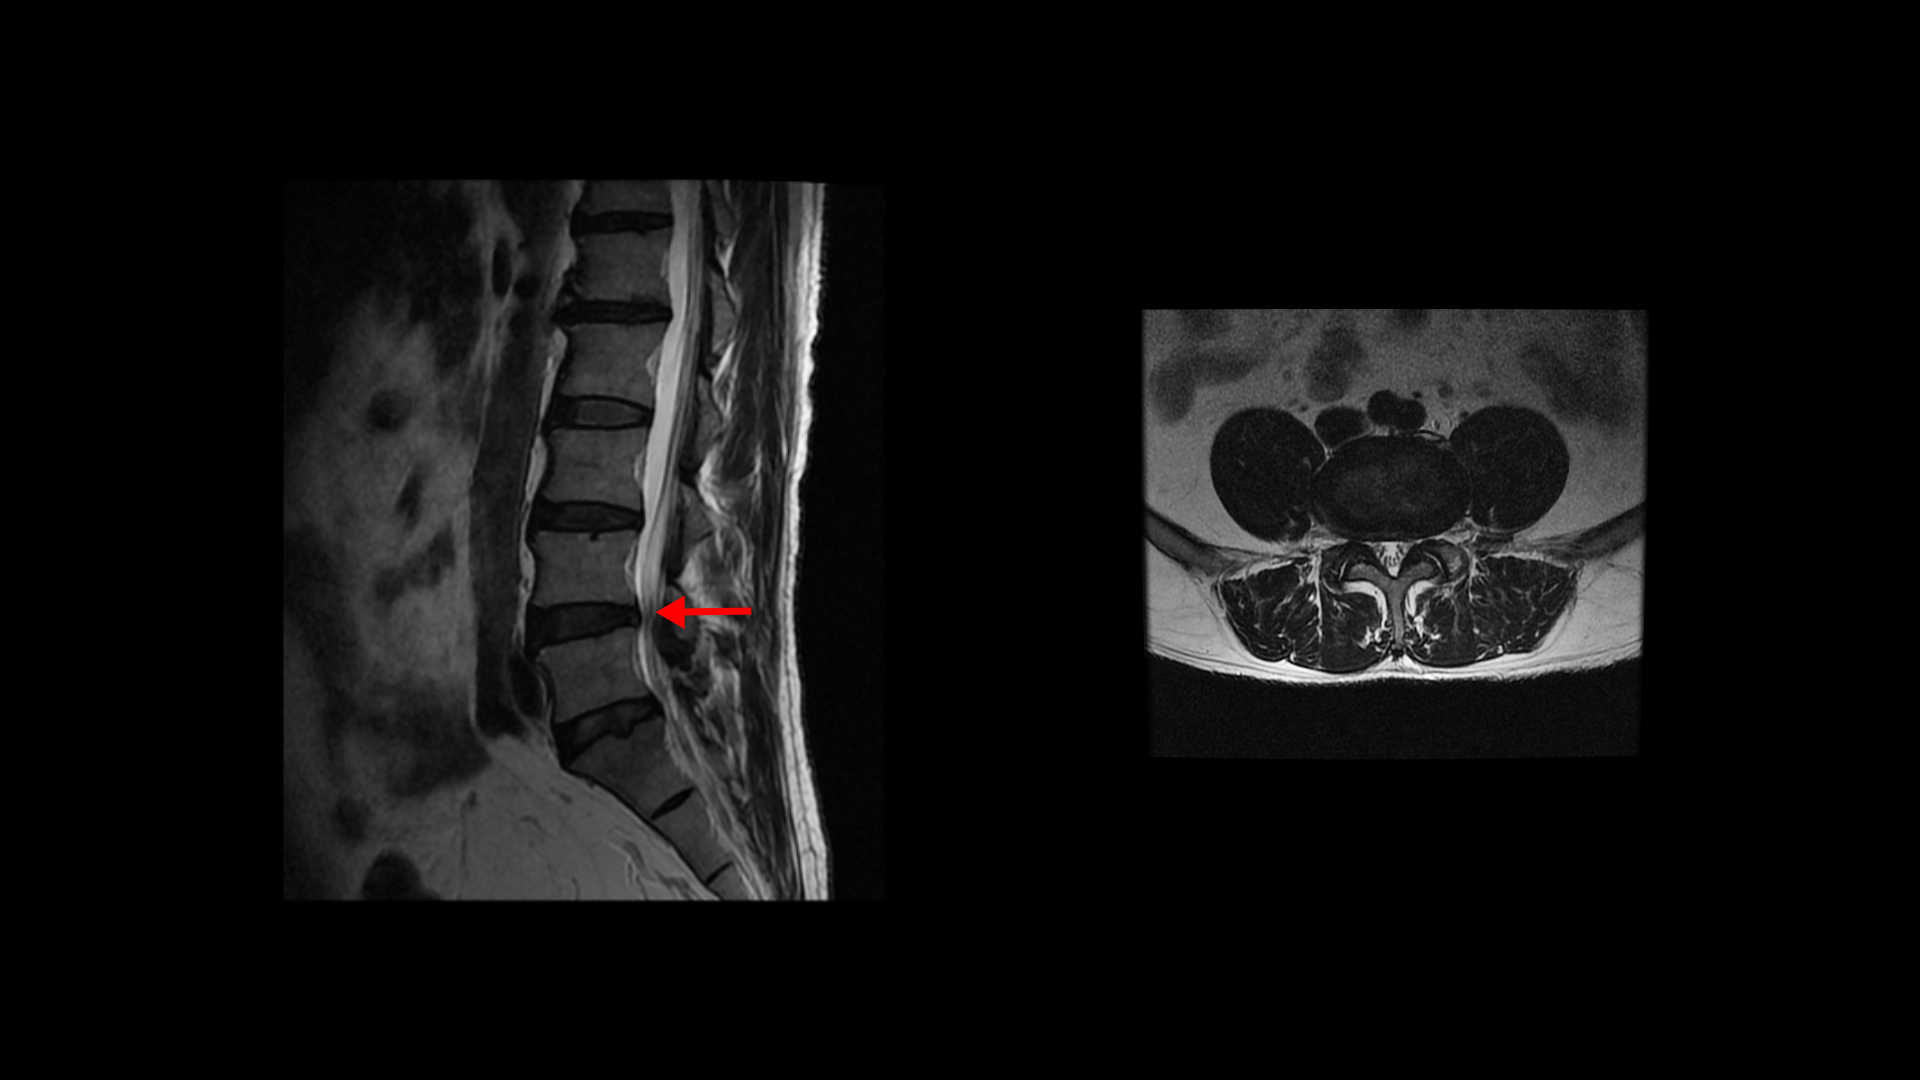

특히 MRI에서 보이는 신경 눌림이 심하지 않을수록 근육 문제일 가능성은 훨씬 더 높아집니다. 이 환자분 MRI를 한번 볼까요? 세 마디에 퇴행성 디스크가 있지만 심하지 않습니다.

4번 5번 마디의 척추관도 협착이 진행되었지만 좁아진 게 많이 심하지 않습니다.

오른쪽, 왼쪽 신경이 빠져나가는 추간공도 조금 좁아지긴 했지만 별로 심하지 않습니다.

이렇게 신경 구멍 좁아짐이 심하지 않으면 근육 문제일 가능성은 훨씬 높아집니다. 그리고 신경 구멍이 많이 좁아져 신경 눌림이 심해 보인다고 하더라도 역시 어느 날 갑자기 한쪽 다리, 엉덩이가 아픈 증상은 근육 문제가 가장 중요한 원인입니다.